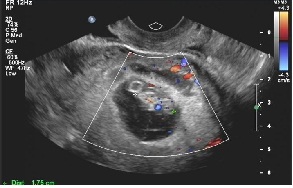

2019年10月29日二超:宫腔内见胚囊,大小31´21´31mm,胚芽长18mm,胎心167次/分。今天顺利毕业!转往产科建卡!